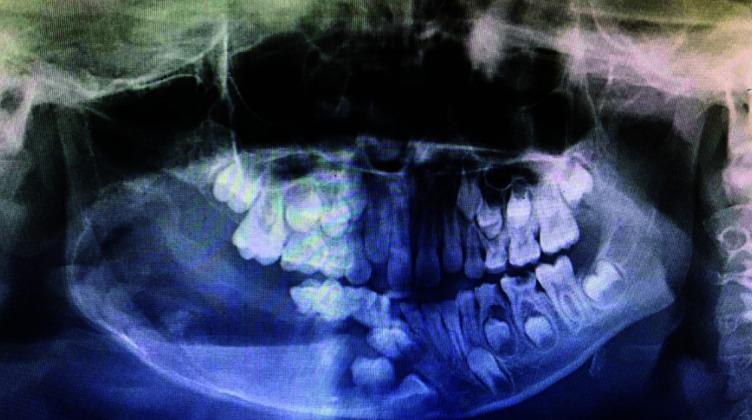

Massive cystic lesions involving a mandible always present a diagnostic and treatment challenge. Unicystic ameloblastoma (UA) is a variant of ameloblastoma encompassing about 6% of ameloblastomas. They represent cystic lesions that reveal clinical and radiographic features of a cyst, but the histopathological features demonstrate a typical ameloblastomatous epithelium lining the cyst. It is a variant of ameloblastoma, usually having clinical and radiographic similarities with dentigerous cysts, hence posing preoperative diagnostic difficulties. Adult treatment protocol cannot be applied to the pediatric population since resection may cause an alteration in craniofacial development leading to functional and esthetical damage, which can directly affect their quality of life. A more conservative approach of enucleating the lesion seems to be a promising treatment modality of UA in the pediatric age group. We present a case of mural variant of UA arising from dentigerous cyst in an 8-year-old male patient.